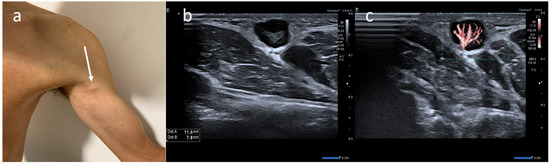

Atypical Sites of Lymphadenopathy after Anti-COVID-19 Vaccine: Ultrasound Features

- Cocco, G.; Pizzi, A.D.; Fabiani, S.; Cocco, N.; Boccatonda, A.; Frisone, A.; Scarano, A.; Schiavone, C. Lymphadenopathy after the Anti-COVID-19 Vaccine: Multiparametric Ultrasound Findings. Biology 2021, 10, 652. [Google Scholar] [CrossRef] [PubMed]